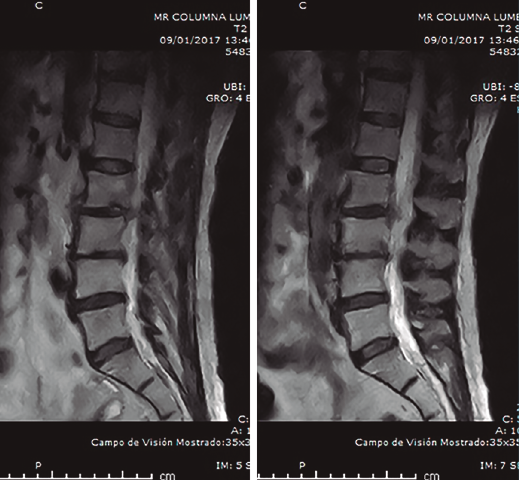

Figura 2. Resonancia magnética inicial realizada en el hospital de origen. Imagen de discopatía muy evolucionada con posible hernia L2/L3. Sagitales T2.

Se realizó analítica completa: hemograma normal, marcadores proteína C reactiva (PCR) y velocidad de sedimentación globular (VSG) claramente elevados, 80 y 63 respectivamente, Rx y RM (Figuras 1 a 4).